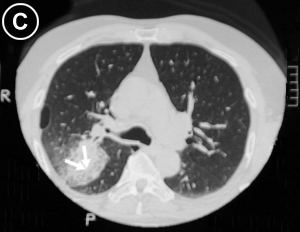

• Corte Tomográfico

a nivel supracarinal:

• Flechas Blancas: Tercio inferior de la lesión tumoral, sólida y se define su borde posterior. Ubicación segmentaria.